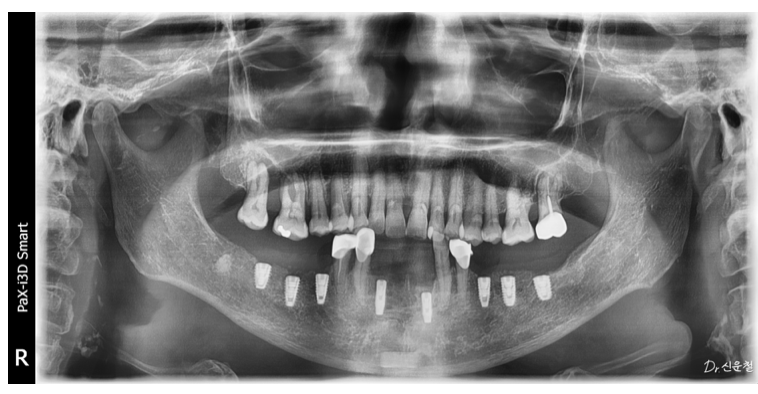

그래서 먼저 아래턱의 뼈 상태를 확인했습니다.

다행히 환자분은

임플란트를 진행할 수 있는 정도의

뼈 상태가 유지되어 있었습니다.

촬영일 : 250825

겉으로 보기에는

두 치아 모두 발치가 필요해 보였지만

자세히 검사해 보니 상황이 조금 달랐습니다.

한 치아는 염증이 넓게 퍼져

발치가 더 안전한 상태였고

다른 치아는

신경치료를 통해 충분히 사용할 수 있는 상태였습니다.